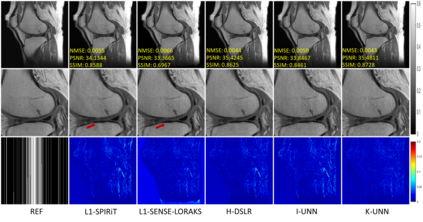

Recently, untrained neural networks (UNNs) have shown satisfactory performances for MR image reconstruction on random sampling trajectories without using additional full-sampled training data. However, the existing UNN-based approach does not fully use the MR image physical priors, resulting in poor performance in some common scenarios (e.g., partial Fourier, regular sampling, etc.) and the lack of theoretical guarantees for reconstruction accuracy. To bridge this gap, we propose a safeguarded k-space interpolation method for MRI using a specially designed UNN with a tripled architecture driven by three physical priors of the MR images (or k-space data), including sparsity, coil sensitivity smoothness, and phase smoothness. We also prove that the proposed method guarantees tight bounds for interpolated k-space data accuracy. Finally, ablation experiments show that the proposed method can more accurately characterize the physical priors of MR images than existing traditional methods. Additionally, under a series of commonly used sampling trajectories, experiments also show that the proposed method consistently outperforms traditional parallel imaging methods and existing UNNs, and even outperforms the state-of-the-art supervised-trained k-space deep learning methods in some cases.